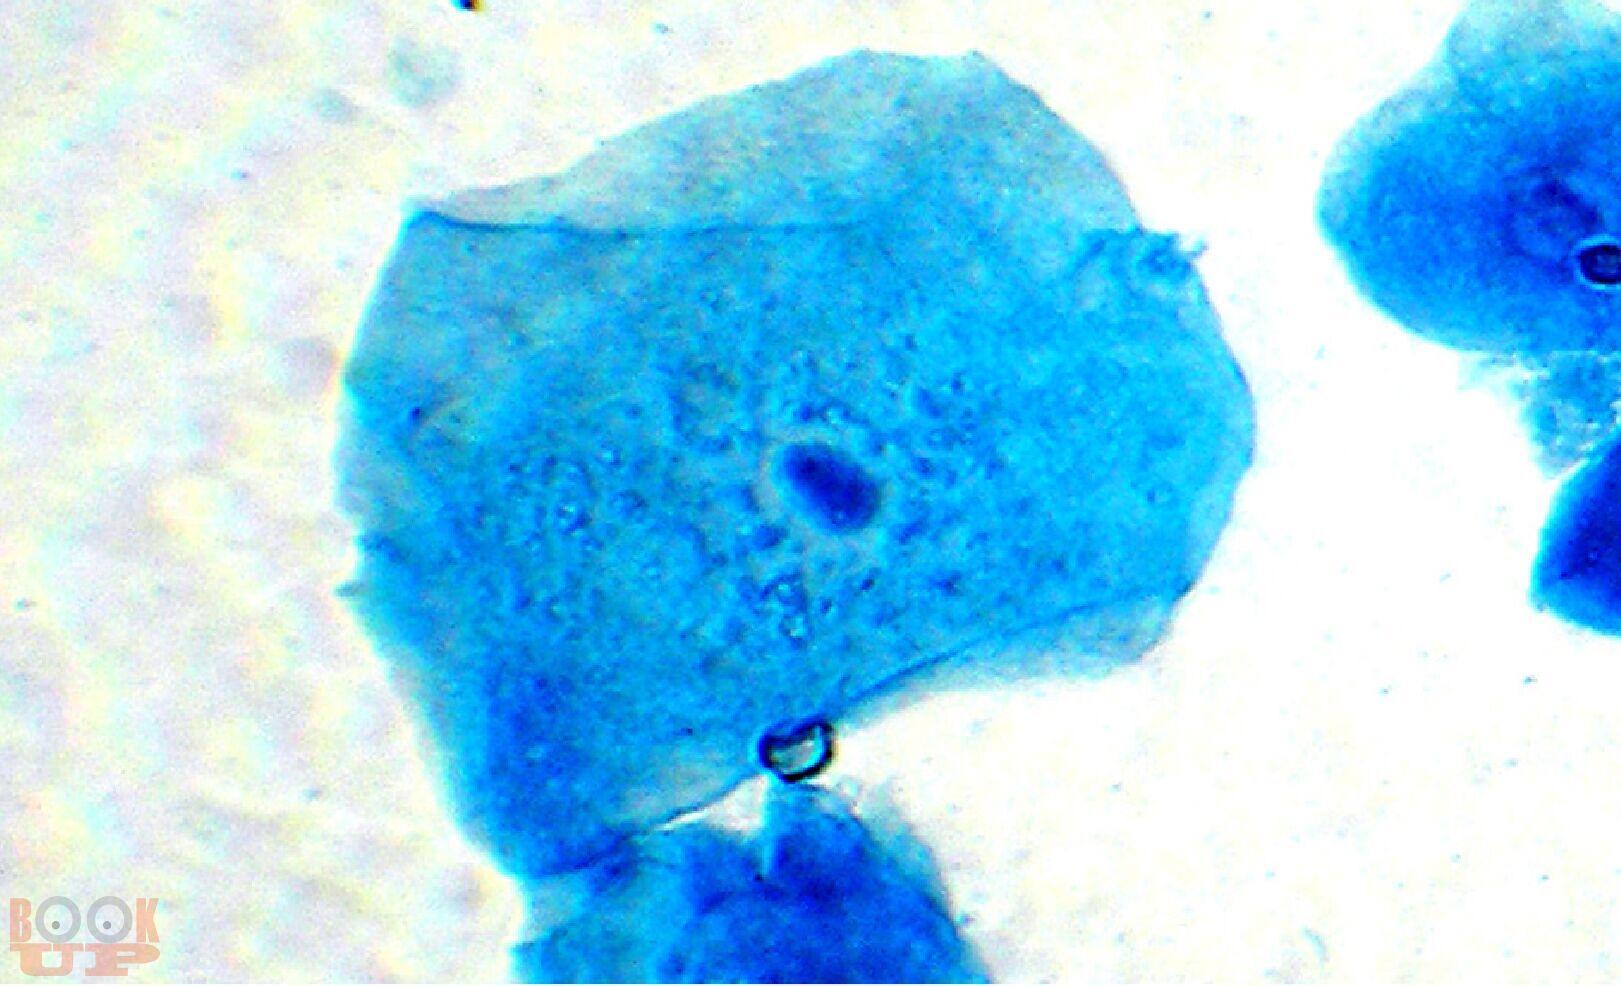

В монографии представлены новые данные об исследовании мочи и желудочного содержимого. Впервые разработаны способы диагностики половой принадлежности мочи по различиям в содержании ядросодержащих и безъядерных клеток и достоверного установления наличия желудочного содержимого на вещественных доказательствах и во внешней среде. В работе приведены результаты исследований о влиянии различных факторов на клеточный состав мочи и на выявляемость желудочного содержимого.